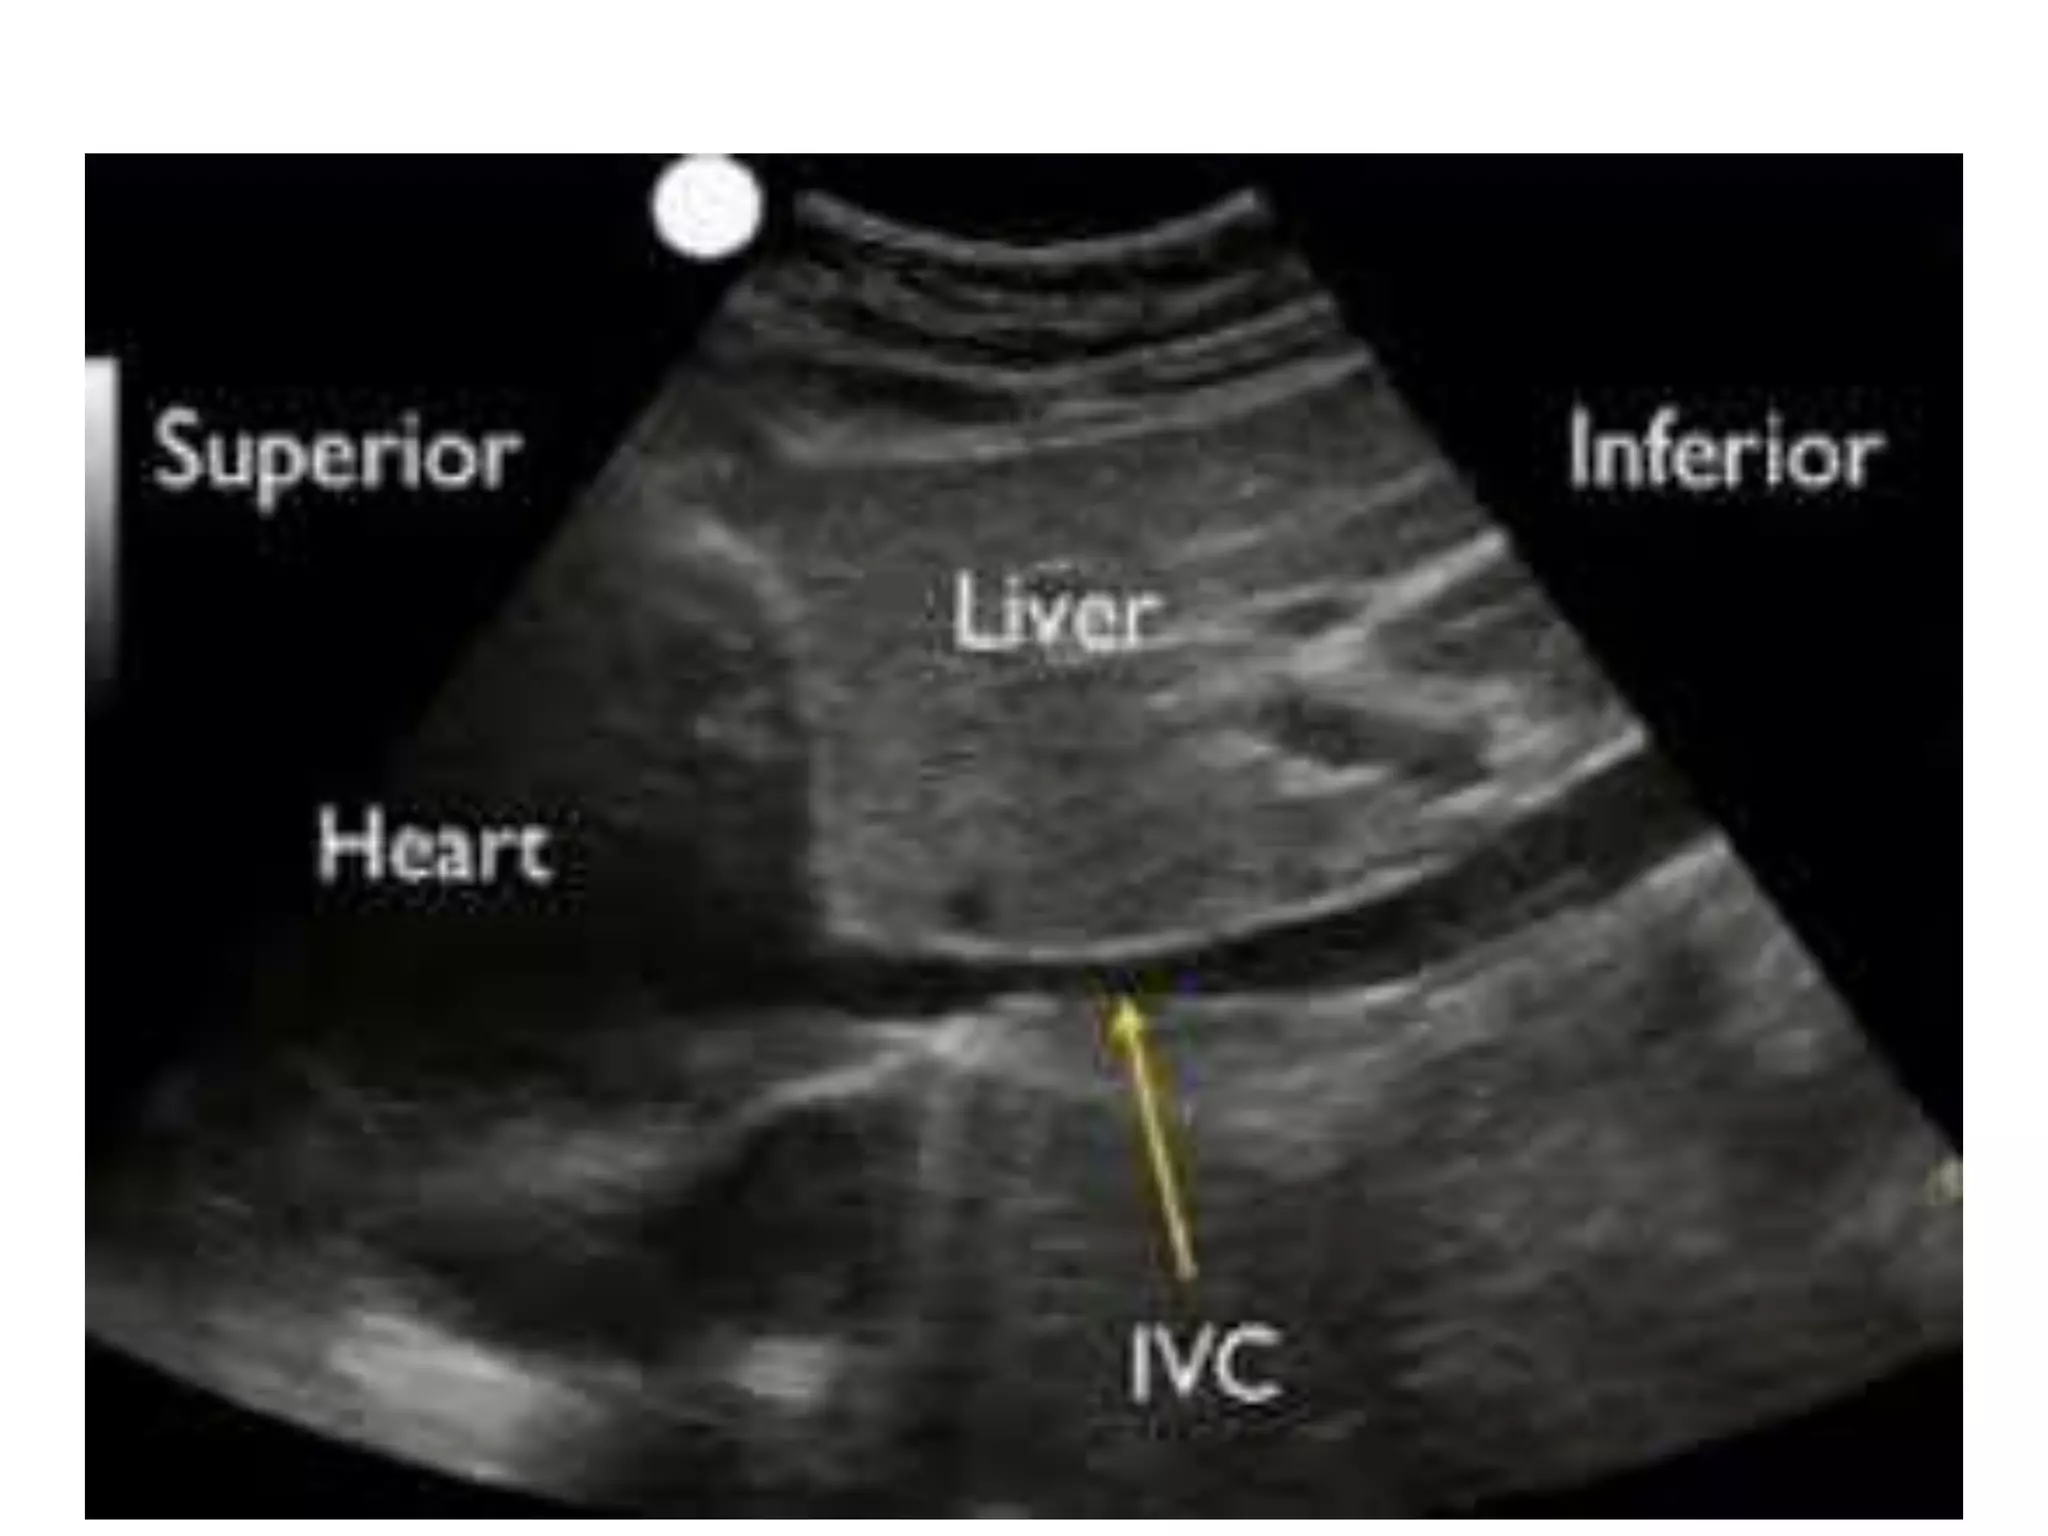

IVC